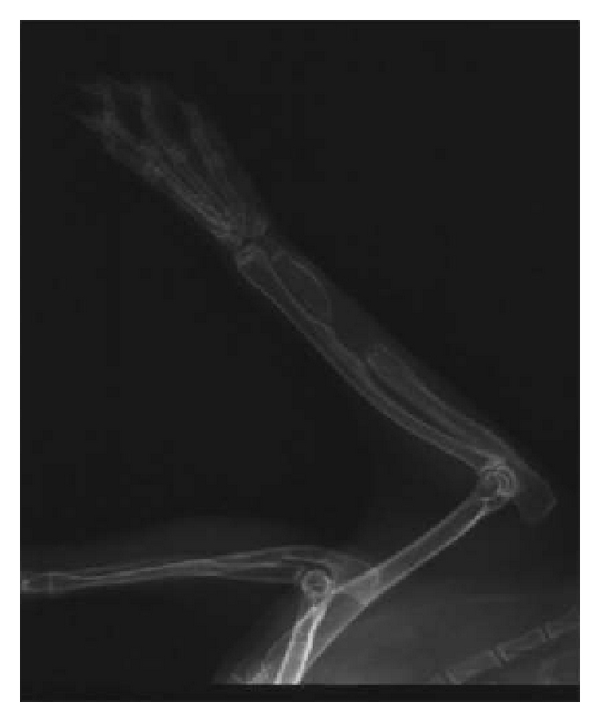

3.2. X-Ray Radiation Examination

X-ray radiation examination was conducted on right upper limb of 30 New Zealand rabbits immediately after surgery. Sufficient amount of scaffolds had been implanted into the bone defect site and the diameter of scaffold was bigger than ulna, indicating that it is a successful modeling for New Zealand rabbits bone defect. Small callus tissue and remaining scaffold can be observed in group A and group B 1 month after implantation; at the same time, periosteal proliferation was found in samples in group C. There was no statistically significant difference among three groups () according to chi-square test. At 2 months, plenty of calluses were expansively grown in group B; big callus volume was formed at the terminals of defect site in group A; no callus was formed in 8 samples of group C, and the difference among three groups was statistically significant () according to chi-square test. After 3 months, the volume of callus in group B was bigger than group A, and group C had marrow cavity sclerosis and bone atrophy which was typical bone nonunion performance. The difference among three groups was also significant (). The effective rate in group A was 14.29% (1 of 7 ulnas was healed), while the effective rate of group B was 33.33% (2 in 6). We excluded 2 dead rabbits in each group which was selected for histology HE staining test in the first 2 months. Figure 2 shows the example radiographs obtained at the 3rd month after surgery in three groups.

(a)

(b)

(c)